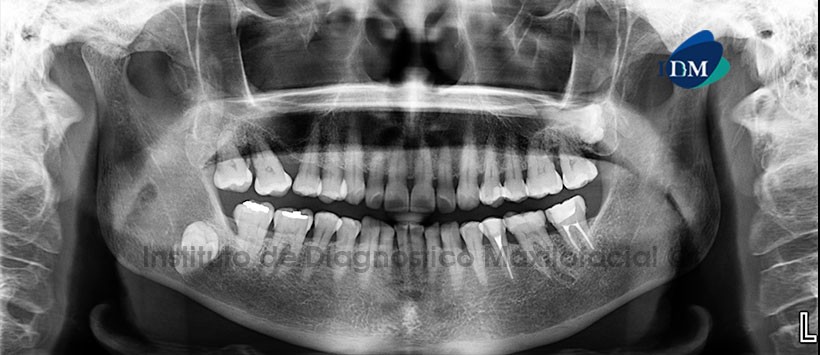

Paciente femenino de 61 años de edad es referido al Instituto de Diagnóstico Maxilofacial (IDM) para su evaluación y diagnóstico.

A la evaluación de la radiografía Panorámica (Figura 1) se apreció la impactación de la pieza 48, en posición transversal y con ligera orientación mesioangular, con el segmento cervical y medio radicular en estrecha relación con el conducto dentario inferior adyacente. A la evaluación de la tomografía computarizada Cone beam mediante cortes axiales, coronales, sagitales (Figura 2) y transaxiales (Figura 3), se encontró la disposición de la pieza 48 incluida, en posición transversal, con el segmento radicular orientado hacia la tabla ósea lingual, ocasionando la conformación de la cara lingual al contorno radicular y disminución parcial del espacio periodontal y folicular. Se evidenció la disposición del conducto dentario inferior en relación directa con la pieza 48, mostrando un recorrido de mesial a distal orientado hacia la tabla ósea lingual e interradicular con respecto a dicha pieza.